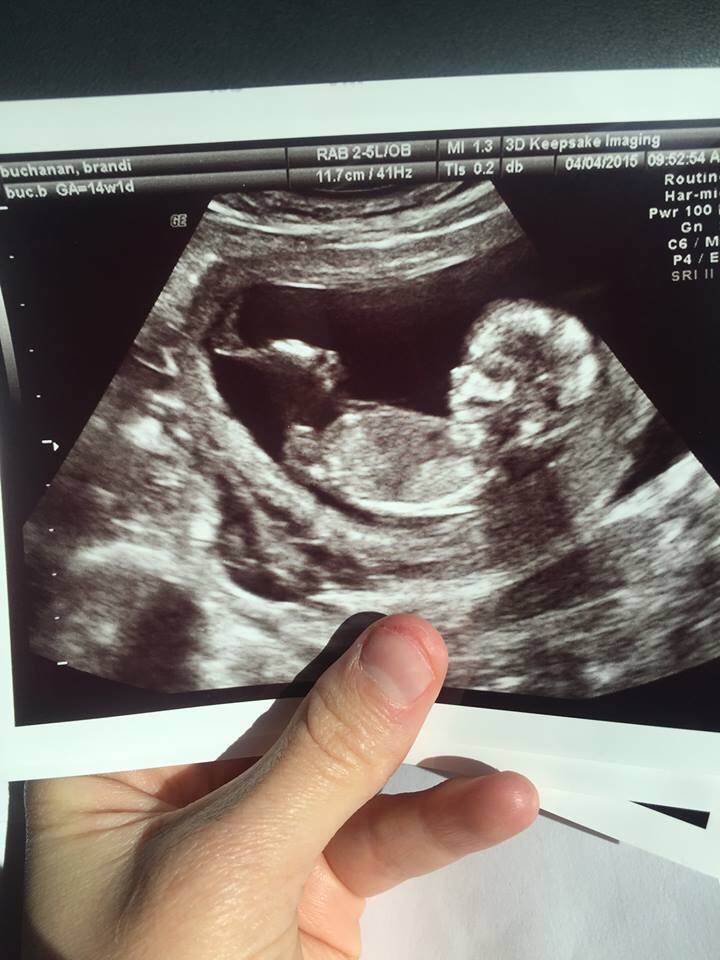

The gender of your baby is revealed at your second scan between 18 and 21 weeks - but theres another test people use to determine if its a boy or girl Credit. At 13 weeks pregnant baby gender ultrasound is mostly done to determine proper development of the baby but it can also help you determine whether the baby is male or female.

Oh I can tell you why they said 80 though. Ultrasounds can now detect a babys gender as early as 12-13 weeks gestation. All babies have a genital tubercle or nub between their legs that develops between 11-13 weeks.

It reported a lower accuracy rate before 12 weeks gestation but concluded 3D ultrasound is a highly accurate and reproducible tool for fetal gender assignment prior to 14 weeks of gestation Another study looked at 496 patients between 11 and 13 weeks plus six days pregnant who requested gender information during their first trimester screening. The flow of urine can sometimes be spotted in a fetus. Around week 12 you can tell the gender with an 80 accuracy at 13 weeks with 95 and so on.

By week 13 to 16 a very clear difference can be seen on ultrasound but keep in mind at 12 to 13 weeks the average baby is only the length of 2 pennies placed side by side and the genital area is the size of a pinhead. Boys and girls genitals develop along the same path with no outward sign of gender until about nine weeks. However its not until 14 or 15 weeks that you can clearly begin to see the differentiated genitalia.